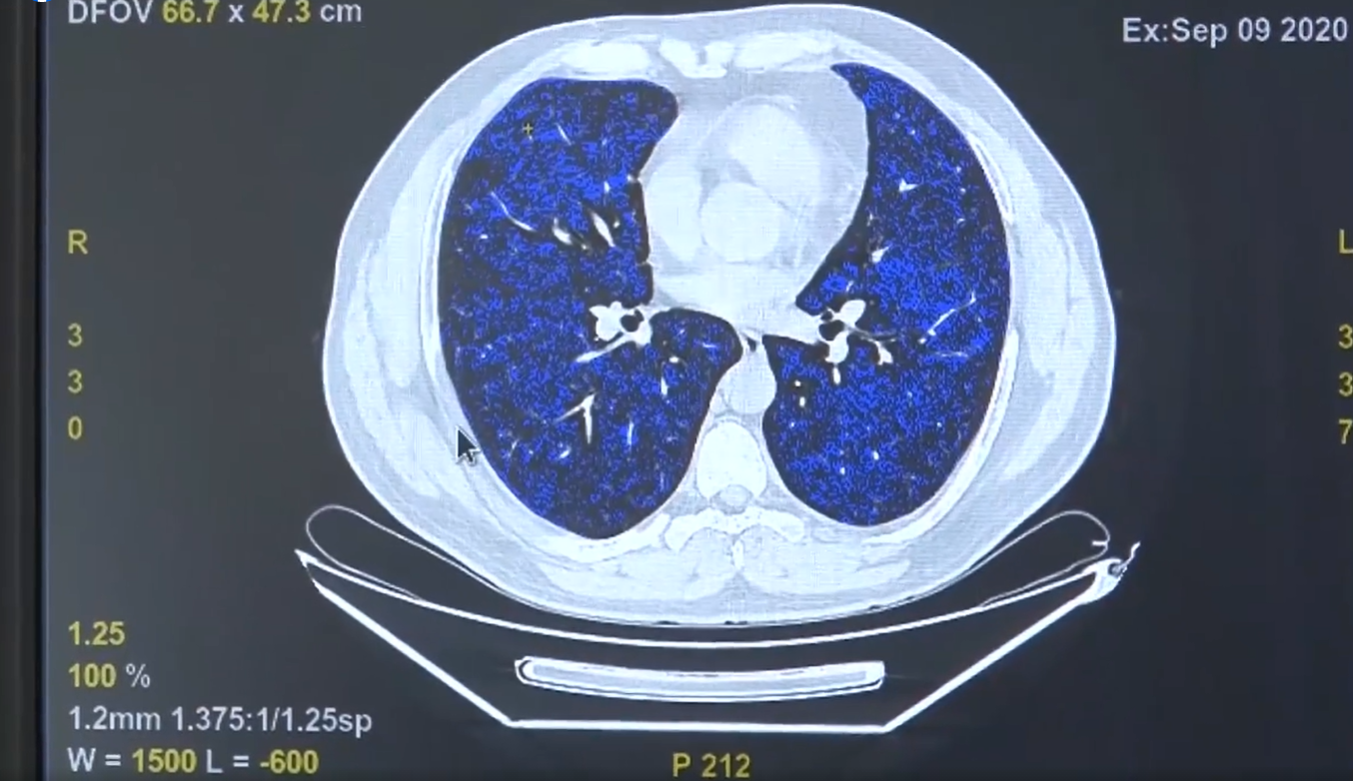

Medicii Spitalului de Boli Infecțioase și Pneumoftiziologie „Victor Babeș” din Timișoara au implementat un soft de postprocesare a investigației imagistice, realizată cu ajutorul computerului tomograf.

Acesta permite o analiză volumetrică a nodulilor pulmonari, ceea ce poate duce la detecția precoce a riscului de cancer în cazul pacienților care au asemenea „pete pe plămâni”.

Potrivit reprezentanților spitalului, imaginea obținută cu ajutorul screeningului imagistic este introdusă în softul stației de postprocesare, fiind oferite mai multe informații, de la volumul nodulului analizat până la elaborarea unui model de predictibilitate, ce prezintă o posibilă evoluție într-un interval de timp de până la un an.

„Analiza din punct de vedere al volumului unui nodul pulmonar este mult mai fidelă decât cea bidimensională. Un nodul nu o să crească niciodată doar în două dimensiuni, pe cele două axe standard, ci are o creștere volumetrică, de multe ori în toate direcțiile. Iar acest soft asta permite, o analiză imagistică mult mai corectă”, spune asist. univ. dr. Diana Manolescu, șef secție radiologie, Spitalul de Boli Infecțioase și Pneumoftiziologie „Victor Babeș” Timișoara.

Softul folosit de radiologii Spitalul de Boli Infecțioase și Pneumoftiziologie „Victor Babeș” Timișoara permite și realizarea unui calcul cu privire la procentul de creștere sau scădere a volumului unui nodul pulmonar într-un interval de timp, în cazul pacienților care efectuează două sau mai multe investigații imagistice cu ajutorul CT-ului.